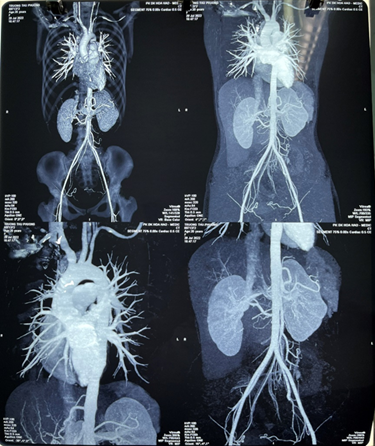

Electrocardiography showed sinus tachycardia 120 bpm (figure 1). Chest x-ray showed normal findings (figure 2). Carotid ultrasound revealed concentric thickening of the

left common carotid artery with 70% stenosis. Chest and abdomen aortic ct scan

with contrast showed stenosis of the right brachiocephalic artery, left common

carotid artery, 50% stenosis of the left subclavian artery and 60% stenosis of

the right renal artery (figure 3).

Figure 3. Chest and abdomen aortic ct scan with

contrast showed stenosis of the right brachiocephalic artery, left common

the right renal artery.

specificity of 97.8%. The chest and abdominal ct angiography showed moderate

renal artery stenosis (60%). 50% stenosis of the left common carotid artery.